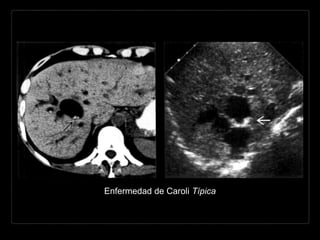

Hallazgos por TC

• áreas hipodensas, pequeñas y múltiples que

son inseparables de la VBIH dilatada.

• + C

• pequeños puntos que refuerzan (radículos

portales) entre la VBIH dilatada.

Enfermedad de Caroli Típica